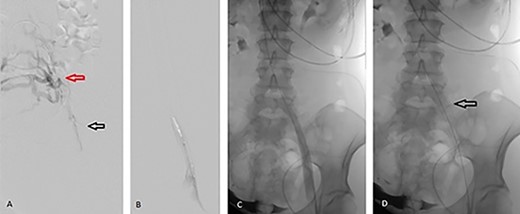

The patient underwent percutaneous thrombectomy of the extensive clot. Intravenous ultrasound (IVUS) revealed stenosis of the left common iliac vein (CIV) and multiple collaterals, indicating chronicity of the condition and compatible with MTS. Balloon angioplasty of the stenotic segment was performed and a 16 × 60 mm stent deployed. Repeat IVUS confirmed a patent stent and completion venogram showed good flow through the FV, CFV, external iliac vein (EIV) and CIV (Fig. 1).

Angiographic images during percutaneous angioplasty of the left CIV. (A) Black arrow demonstrates left CIV stenosis secondary to anatomic compression with extensive clots. Red arrow demonstrates the collateral venous circulation, indicating chronicity of MTS. (B) Balloon angioplasty of the left CIV. (C) Left CIV patent post angioplasty. (D) Arrow demonstrates 16 × 60 mm stent deployed across the left CIV.